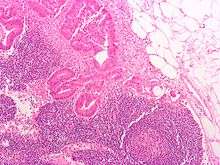

Micrograph of a mesenteric lymph node with adenocarcinoma

Lymph nodes may become enlarged due to an infection, tumour or inflamed due to leukemia. This increase in size is primarily due to an elevated rate of trafficking of lymphocytes into the node from the blood, exceeding the rate of outflow from the node. They may also be enlarged secondarily as a result of the activation and proliferation of antigen-specific T and B cells (clonal expansion). In some cases, where there is no infection they may still feel enlarged due to a previous infection. Lymphogranuloma venereum is a sexually transmitted infection that travels through the lymphatics and targets lymph nodes where the bacteria multiply. Enlarged and painful lymph nodes can result.